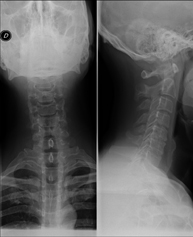

- Cervical spine X-ray

This technique uses X-ray rendered imaging for examining the cervical spine. Indicated for: trauma, cervical pain.